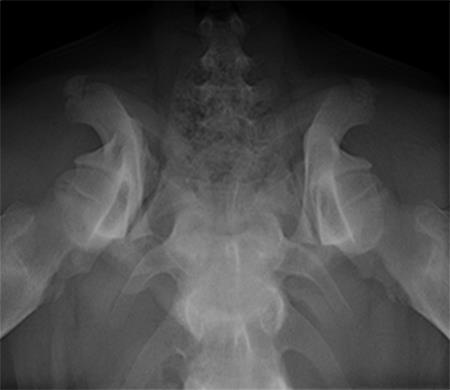

A 5-month-old spayed female labrador retriever puppy weighing 22.0 kg presented with bilateral hind limb weakness and a bunny-hopping gait in the hind limbs. Physical examination revealed bilateral hip instability (positive Ortolani sign) and mild pain on full extension of the hips. Slight crepitus was palpated in the left hip. The gluteal muscles appeared to have mild atrophy. The neurological exam was normal. Radiographic examinations revealed bilateral hip subluxation and a distraction index of 0.5 of the right hip and 0.7 of the left hip (Fig 3). No evidence of osteoarthritis was observed.

A 4-month-old female boxer puppy weighing 15.0 kg presented with bilateral hind limb weakness and reluctance to walk. Physical examination revealed bilateral hip instability (positive Ortolani sign) and severe pain on full extension of the hips. The neurological exam was normal. The radiographs revealed bilateral hip subluxation and a distraction index of 0.65 of the right hip and 0.6 of the left hip (Fig 7). Very mild osteoarthritis was seen and femoral head coverage by the dorsal acetabular rim was good (Fig 8). Angles of subluxation (10° R and 20° L) and reduction (30° R and 40° L) of the hips were measured under anesthesia.